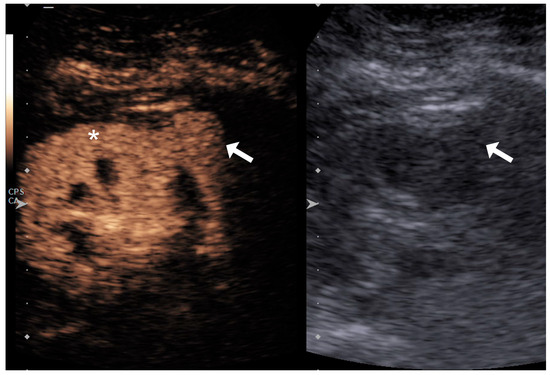

4.1. Qualitative Evaluation